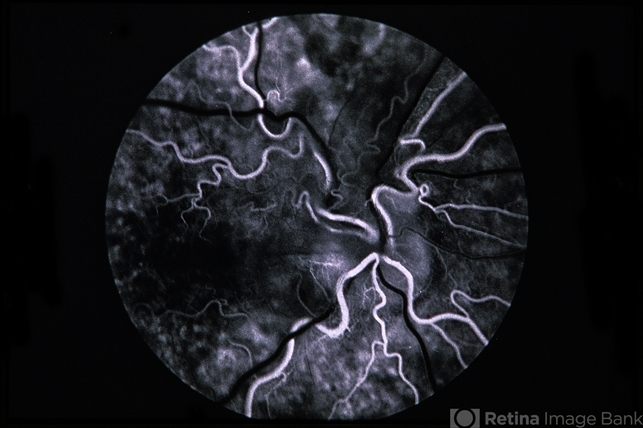

- Combined Hamartoma of the RPE

- combined hamartoma, retinal pigment epithelium (RPE) hamartoma

- Fluorescein angiogram of second patient.